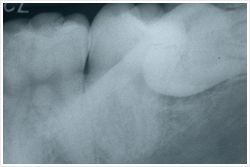

特に「親知らず」。

歯の知識のページでも触れていますが、「異常な生え方をして歯磨きができない場合・・・」、「親知らずのためにかみ合わせがおかしくなっている場合・・・」などは抜いた方が良いです。

たとえばこんな感じのもの・・・

よく「親知らずが腫れて痛い」と聞きますよね。

これは歯が腫れるのではありません。

歯磨きが行き届かないため歯垢がたまり、まわりの組織に炎症がおきて腫れるのです。

大昔に比べ食生活が変わり、人間の顎は小さくなって親知らずまでうまく並ばない。

そう一種の「文明病」なのです。

当院ではこんな難しい親知らずの抜歯もできるだけお引き受けしています。

大学病院を紹介されたけれど、「ちょっとおっくう」 「なかなか時間がとれない」 という方は1度ご相談ください。